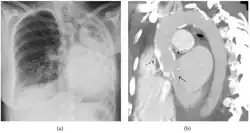

El diagnóstico del fibrotórax suele basarse en una historia clínica adecuada combinada con técnicas de imagen como la radiografía de tórax o la tomografía computarizada.[3] Estas herramientas detectan el engrosamiento pleural y la fibrosis alrededor de los pulmones.[7] La presencia de una corteza engrosada, con o sin calcificación, es una característica común en las imágenes.[3] Las tomografías computarizadas diferencian mejor si el engrosamiento se debe a depósitos de grasa o a fibrosis verdadera.[3]

En casos graves, el pulmón afectado puede perder volumen[7] y el mediastino puede desplazarse hacia el lado afectado.[3] Una reducción del tamaño de un lado del tórax en las imágenes sugiere cicatrización crónica.[6] Los signos de la enfermedad subyacente que causa el fibrotórax también se observan ocasionalmente en la radiografía.[6] Las pruebas de función pulmonar suelen mostrar hallazgos compatibles con una enfermedad pulmonar restrictiva.[6]

Radiografía de tórax (izquierda) y tomografía computarizada (derecha) que muestran fibrotórax. -